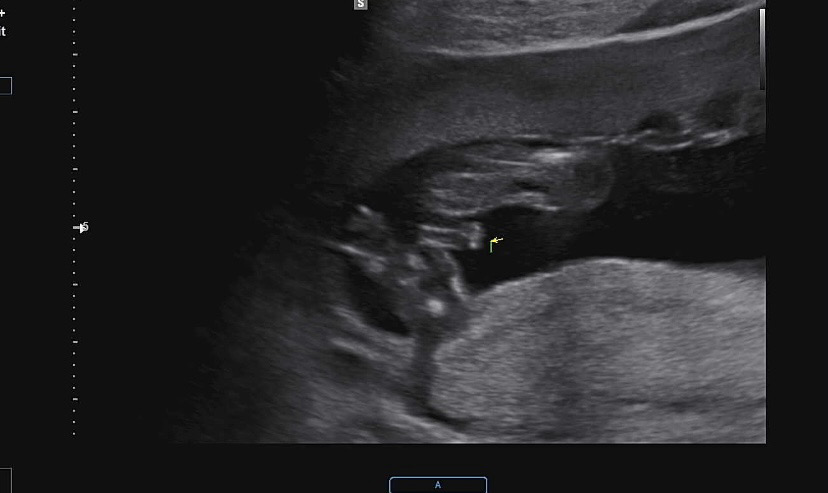

16์ฃผ์ฐจ 2์ฐจ ๊ธฐํ์ ๊ฒ์ฌ ํ๊ณ ์ฑ๋ณ๋ ํ์ธํ๊ณ ์์ด์! ์ฒ์์ ์์ ํ ๋ค๋ฆฌ๋ฅผ ๊ผฌ๊ณ ์์ด์ ์๋ณด์ฌ์ฃผ๊ธธ๋ ์ค์ด ํ๋ฒ ๋ ๋ณด์๊ณ ํ์ ์ ๊ฒ์ฌํ๊ณ ๋ค์ ํ ๋ฒ ๋ดค๋๋,,๐ถ๏ธ ์ด๊ฒ ๊ทธ ์ผ๊ฐ์ ์ธ๊ฐ์ใ ใ ใ ใ ใ ์ ๋ฒ์ ๊ฐ๋๋ฒ์ผ๋ก ์ด๋์ ๋ ์์์ ํ๋๋ฐ ์กด์ฌ๊ฐ์ด ์ ๋ง ๋ง๋๊ฑด๊ฐ์? ํ์ดํ ...๐ฅน